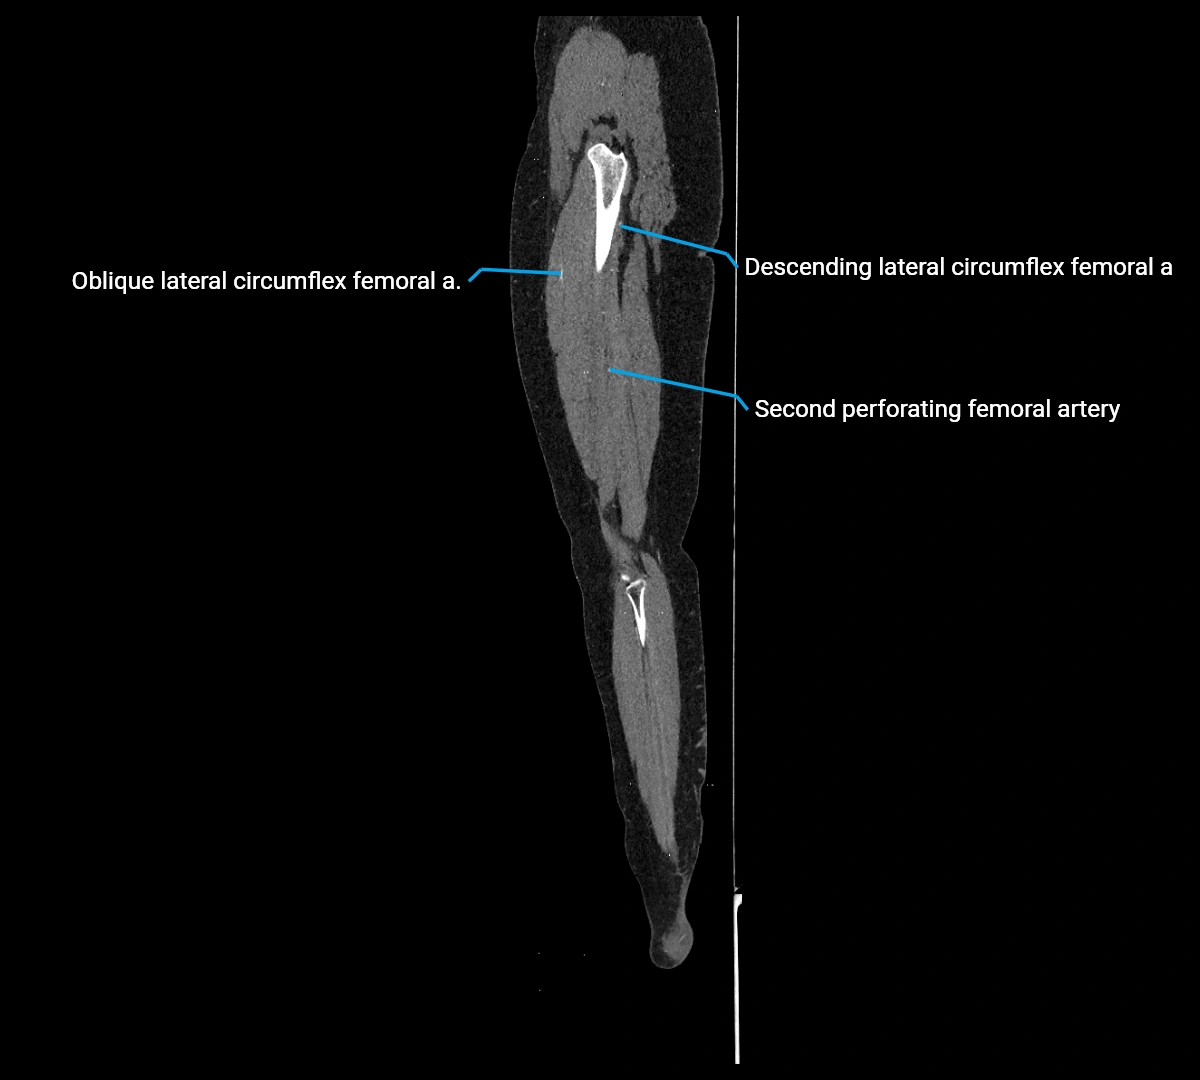

Contrast-enhanced CT (CTA):

• Gold standard for abdominal aortic imaging

• Provides excellent detail of lumen, wall, aneurysm, thrombus, and branch vessels

• Multiplanar and 3D reconstructions help in aneurysm measurement, stent graft planning, and dissection evaluation

• Detects acute rupture, traumatic injury, or occlusion with high sensitivity